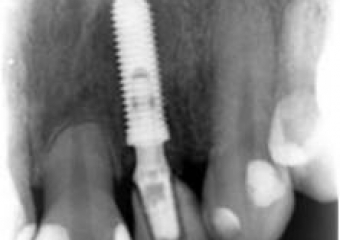

Imagem do dente provisório fixo sobre o implante - Clínica Cliniface

Imagem do dente provisório fixo sobre o implante